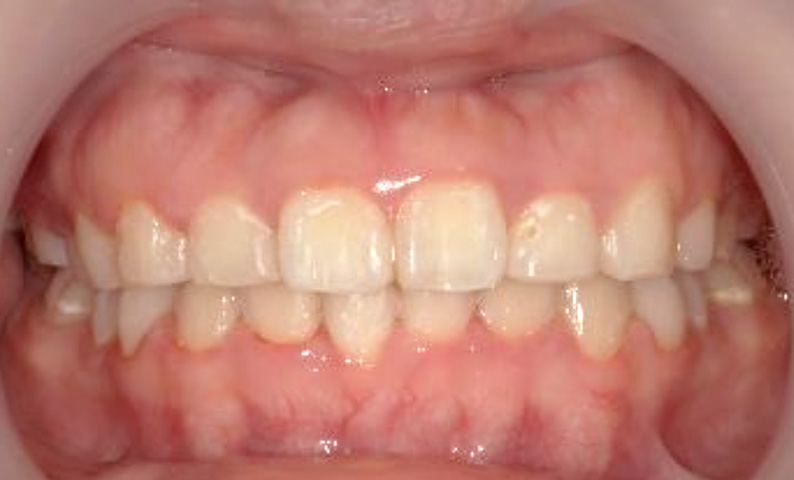

症例_024 上顎だけの部分矯正

治療期間:7ヶ月金額:30万円+税女性前歯のガタガタ上の前歯だけ

| Before | After |